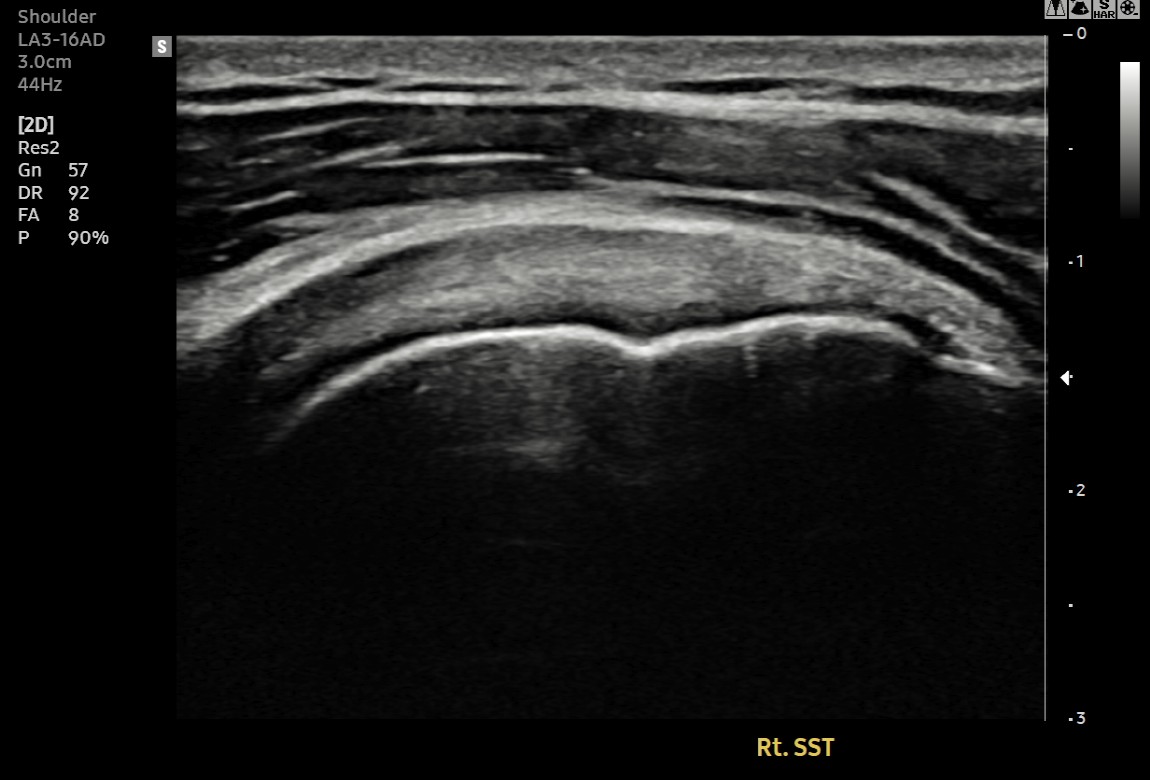

초음파와 MRI 검사 결과, 환자분은 회전근개 극상건의 점액낭면 부분파열 상태였습니다. 파열 크기는 약 1cm, 근육 위축이나 지방 변성은 심하지 않았습니다.

초음파 검사 결과, 이전에 검게 보이던 파열 부위가 정상 인대처럼 하얗게 재생되어 있었습니다.